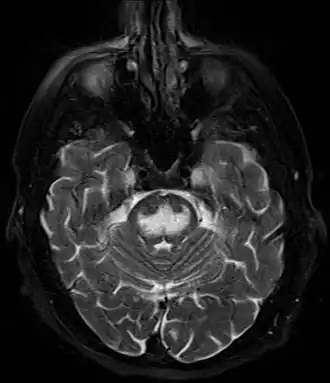

- Визуализация головного мозга при синдроме осмотической демиелинизации[18]

- Магнитно-резонансная томография (МРТ)

Чаще изменения локализуются в нижней части моста имеют вид трезубца или бабочки. Но могут быть также в базальных ганглиях, среднем мозге и белом веществе субкортикальных областей. Накопление контрастного вещества возможно.

Ранние изменения (в первые 24 часа от развития тетрапареза): гиперинтенсивный сигнал (что говорит об ограничении диффузии) в режиме DWI. Изменения в режимах Т1- (гипоинтенсивный сигнал) и Т2-ВИ (гиперинтенсивный) могут развиваться не сразу (до 2 недель). Другие последовательности: FLAIR: гиперинтенсивный, ADC: низкий сигнал